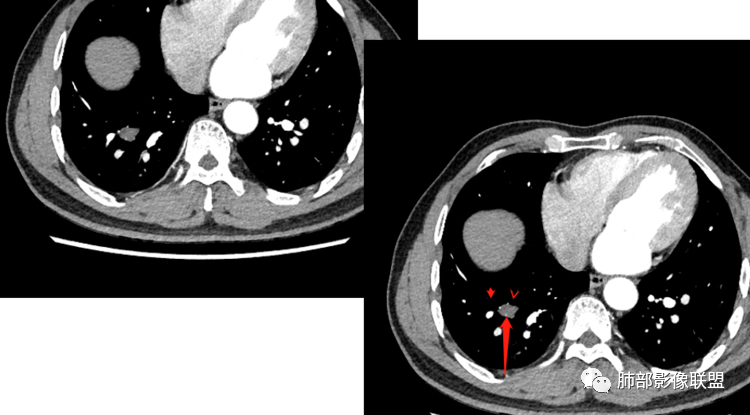

2.右肺下叶背段胸膜下块影,边界清楚光整,上下极见磨玻璃晕,未见明显分叶毛刺和棘状突起,未见胸膜凹陷或胸壁侵入。密度均匀,轻度不均匀强化。未见支气管进入。

3.右肺中叶外侧段胸膜下散在小片影,磨玻璃密度为主,边界不清,支气管相关。符合炎性特征!

4.右肺下叶基底段支气管血管束旁小结节影,边界清楚,强化不明显。注意,这结节在“遥远的”基底段。

右肺下叶占位,胸膜下,与胸膜关系密切;

密度均匀;糊墙,边缘膨隆为主;

部分血管推移。

血管也是稍推移,在边缘,病灶密度均匀,边缘稍收缩;均匀强化;

这两个病灶的密度、强化、形态、边缘、与血管的关系类似;还是一元论吧。